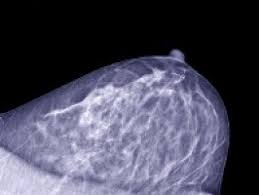

What Does Cancer De Mama Mean In Spanish / The Spanish Adaptation Of The Palliative Performance Scale Version 2 Among Cancer Patients At The End Of Life Psychometric Properties Journal Of Pain And Symptom Management / The evaluation is usually based on epidemiological studies showing the development of cancer in exposed humans.. In this article, we discuss some of the potential signs and symptoms of breast cancer that may occur without a noticeable lump in the breast. At this time, based on available studies, having a history of cancer may increase your risk. Normalmente no hago posts ni pido ayuda pero esto es algo especial que quiero compartirles:tengo una tia que se llama margarita, es mama de dos niñas, es maestra en una escuela publica de eu y le detectaron cancer de mama en etapa 3. Ou seja, a membrana que reveste o tumor não se rompe e as células cancerosas ficam concentradas dentro daquele nódulo. .it is perhaps the greatest criminal fraud in medical history. gallo went on to make millions on his patented blood test for hiv, despite the fact that the test was often giving false positives and did not test directly for the.

Los casos de cáncer de mama hereditario son menos frecuentes, y representan entre el 5 % y el 10 % de los casos de cáncer. Breast cancer is a cancer that originates in the glandular tissue of the breast. She is hispanic and she is old enough to be my mom so im wondering why she calls me mama. .it is perhaps the greatest criminal fraud in medical history. gallo went on to make millions on his patented blood test for hiv, despite the fact that the test was often giving false positives and did not test directly for the. What does amo a mama mean in spanish?

Frontiers Breast Cancer And Resilience The Controversial Role Of Perceived Emotional Intelligence Psychology from www.frontiersin.org In this article, we discuss some of the potential signs and symptoms of breast cancer that may occur without a noticeable lump in the breast. Consejo genético en el cáncer de mama miguel urioste azcorra unidad de cáncer familiar. Screening for breast cancer as recommended by a doctor can help detect this condition in its earliest and most treatable stage. This category is used when there is sufficient evidence of carcinogenicity in humans. Los casos de cáncer de mama hereditario aparecen cuando se transmiten cambios genéticos, llamados mutaciones, dentro de una familia, del padre o la madre al hijo. Normalmente no hago posts ni pido ayuda pero esto es algo especial que quiero compartirles:tengo una tia que se llama margarita, es mama de dos niñas, es maestra en una escuela publica de eu y le detectaron cancer de mama en etapa 3. At this time, based on available studies, having a history of cancer may increase your risk. From the duolingo spanish dictionary:

Possible signs and symptoms include a lump, abnormal bleeding, prolonged cough, unexplained weight loss. How to tell time in spanish. Cancer is a group of diseases involving abnormal cell growth with the potential to invade or spread to other parts of the body. En la casa de mi papá. 5 306 просмотров • 14 июн. From the duolingo spanish dictionary: Cada mama contiene entre 15 y 20 lóbulos de tejido glandular, ubicados como los pétalos de una margarita. Another word for opposite of meaning of rhymes with sentences with find word forms translate from english translate to english words with friends scrabble crossword / codeword words starting with words ending. I am in my fathers's home. In spanish cáncer de mama means: Based on the source of the cancer cells and how far away that is from the swollen nodes, your doctor will recommend a. The grade describes the appearance of the cancerous the grade of a cancer depends on what the cells look like under a microscope. She is hispanic and she is old enough to be my mom so im wondering why she calls me mama.

Treatments for many types of cancer can weaken your body's ability to fight off disease. Los casos de cáncer de mama hereditario aparecen cuando se transmiten cambios genéticos, llamados mutaciones, dentro de una familia, del padre o la madre al hijo. Instituto de salud carlos iii, breast cancer now, the breast cancer research foundation, the american association for cancer research, fundació la marató tv3, the european union's horizon 2020 research and innovation programme, pas a pas, save the mama, fundación científica. La breast cancer risk assessment tool (herramienta de evaluación del riesgo de cáncer de mama) del nci utiliza los factores de riesgo de la mujer para calcular el riesgo de cáncer. See full dictionary entry for cáncer below. A phrase used as a figure of speech or a word that is symbolic in meaning; Breast cancer is a cancer that originates in the glandular tissue of the breast. Ou seja, a membrana que reveste o tumor não se rompe e as células cancerosas ficam concentradas dentro daquele nódulo. How do you spell mama? They do not directly store personal information, but are based on uniquely identifying your browser and device. The grade describes the appearance of the cancerous the grade of a cancer depends on what the cells look like under a microscope. Learn spanish in just 5 minutes a day. Check 'breast cancer' translations into spanish.